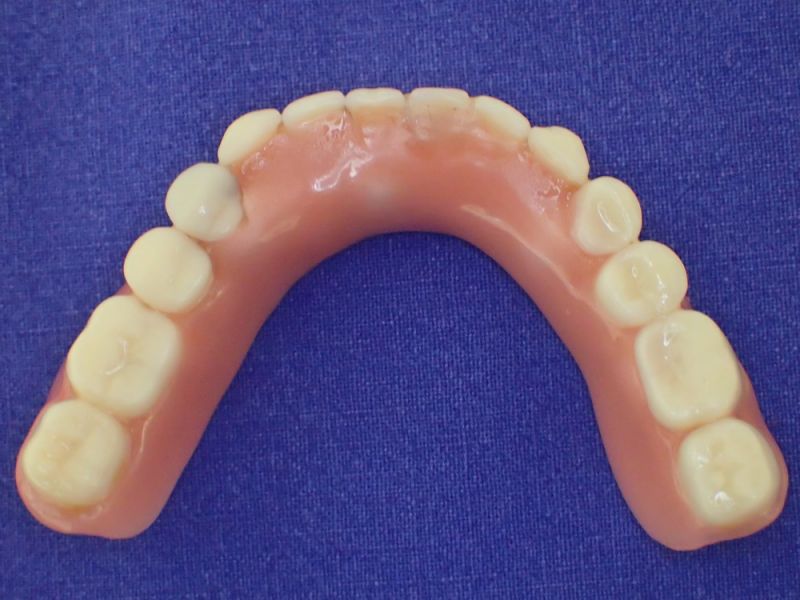

2007 wurde diese implantatgestützte Versorgung erstellt. Die 8 Implantate wurden allesamt hier inseriert und befinden sich bis heute, vollkommen unverändert in Funktion.

Nach inzwischen 12 jähriger Tragedauer wurden alle Kunststoffteile erneuert, das metallische Grundgeroüst der Arbeit erhalten und die Arbeit befindet sich in einem Zustand, der sich weitgehend an der Ersterstellung orientiert.

Bei derartigen Arbeiten ist es tatsächlich möglich grundlegende Konstruktionsmerkmale einer alten Arbeit zu übernehmen und Verschleißteile aus Kunststoff zu erneuern.

Im Prinzip ist das beliebig oft möglich und für den Patienten mit einer enormen Kostenersparnis verbunden.